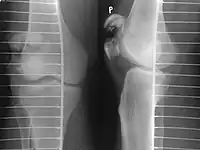

Transverse fracture of patella

Comminuted fracture of patella

Osteochondral fracture of patella

Vertical patella fracture